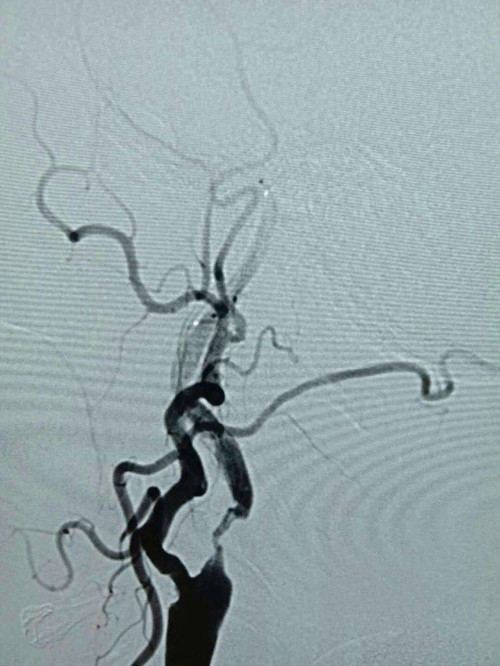

由于患者发病时间为3小时,神经内科医生立即通知介入中心小组成员,同时与家属交代病情,经家属同意,在导管室为患者进行股动脉穿刺。10分钟内穿刺成功,20分钟造影完成。造影结果显示右侧颈内动脉起始处闭塞,无良好代偿。医生给予微导管造影,判断闭塞段长度为15mm,缓慢注射阿替普酶5mg,血管内血栓逐渐溶解。因前段闭塞,仍未见有效血流,与家属再次沟通,决定开通闭塞的右侧颈内动脉。经过紧张、迅速的介入治疗,球囊扩张血管完成,闭塞段开通,残余狭窄85%,前向血流维持2a级,手术顺利完成。术后复查头CT未见出血,狭窄处择期支架成形治疗。术后患者神志清晰,言语较前流利,左侧肢体肌力由0级变为5级弱。